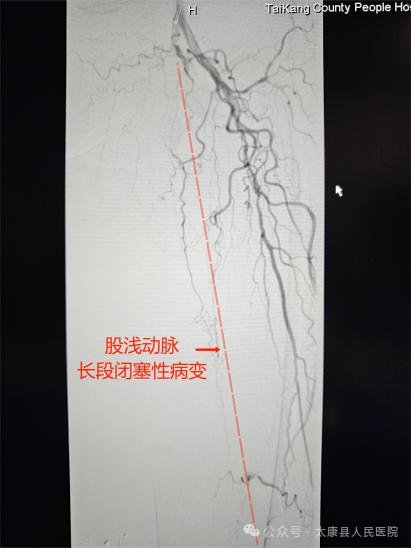

术前造影

面对挑战,介入血管外科团队迅速启动多学科会诊(心内科、肾内科、ICU),结合CTA影像精准评估,制定个体化手术方案。术中采用"双向穿刺+内膜下血管成形+血栓清除+支架置入"等技术,在DSA精准引导下,仅通过大腿1个针眼大小的切口,成功开通闭塞血管:减容后股浅动脉置入支架,足部PPL弓显影,溃疡区染色,血供恢复。手术全程2小时,出血量不足10毫升,术后患者下肢血流即刻恢复,疼痛感消失。

94岁的老奶奶因下肢疼痛、足趾发黑坏死被紧急送至我院。经检查发现,其左下肢股浅动脉存在长达30厘米的完全闭塞,下肢严重缺血导致足趾坏疽,若不及时干预,不仅面临截肢风险,更可能因感染危及生命。高龄、基础病复杂、血管条件极差……重重难关让救治难度陡增。